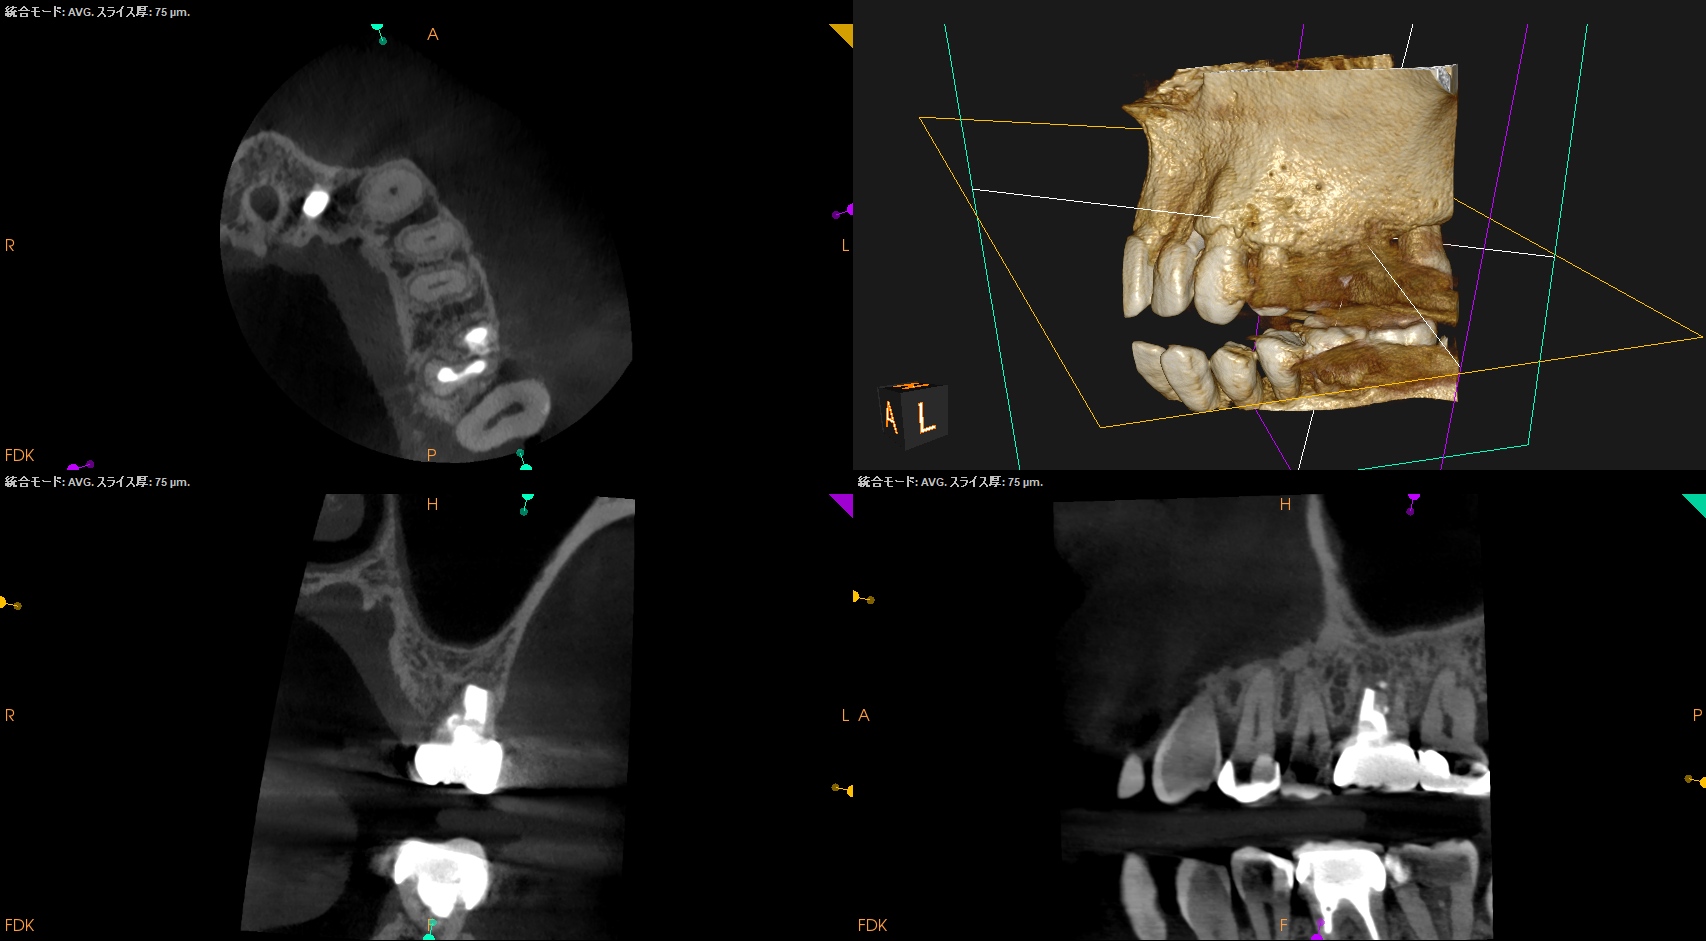

1年以上前に, #14 Intentional Replantationを行っていた。

術前にSinus tractがあり、

3根管全てがここまで大きく拡大形成されており、

DBとPがつながっている。上顎第2大臼歯のような第1大臼歯で、

歯根を取り囲むように歯槽骨が溶けている。

垂直性歯根破折が疑われる。

そして、頬側の歯槽骨がほとんどない。

PA, CBCTも撮影した。

#14

MB

DB

P